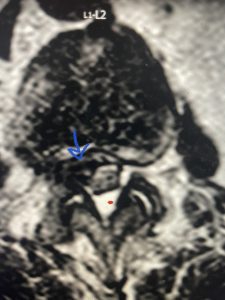

Epidural lipomatosis is a relatively rare condition where normally present fat in the epidural space is hypertrophied and can cause severe thecal sac compression. It is generally deposited more in the lateral and dorsal epidural space. This can be caused by long term steroid use and obesity, but also can be idiopathic. He had done well until more recently had developed low back pain with bilateral thigh pain and numbness. He had difficulty walking because of the pain. A new MRI (Fig 5) revealed that he had developed severe degeneration of the L1-2 segment above his prior decompression and fusion with a large extruded disc/osteophyte, right greater than left with severe thecal sac compression. He also had some residual T12-L3 residual epidural lipomatosis.

(Figs 5a): Sagittal (a) and axial (b) T2-weighted lumbar MRI demonstrating status post lumbar decompression and insitu fusion L2-5 now well decompressed (blue dash) with development of new (red arrow) severe stenosis and with superimposed right L1-2 disc herniation (blue arrow)

(Figs 5b)